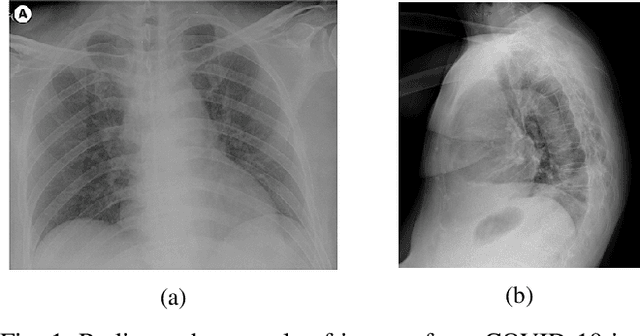

Abstract:Confronting the pandemic of COVID-19 caused by the new coronavirus, the SARS-CoV-2, is nowadays one of the most prominent challenges of the human species. A key factor in slowing down the virus propagation is the rapid diagnosis and isolation of infected patients. Nevertheless, the standard method for COVID-19 identification, the Reverse transcription polymerase chain reaction (RT-PCR) method, is time-consuming and in short supply due to the pandemic. Researchers around the world have been looking for alternative screening methods. In this context, deep learning applied to chest X-rays of patients has been showing promising results in the identification of COVID-19. Despite their success, the computational cost of these methods remains high, which imposes difficulties in their accessibility and availability. Thus, in this work, we propose to explore and extend the EfficientNet family of models using chest X-rays images to perform COVID-19 detection. As a result, we can produce a high-quality model with an overall accuracy of 93.9%, COVID-19, sensitivity of 96.8% and positive prediction of 100% while having about 30 times fewer parameters than the baseline literature model, 28 and 5 times fewer parameters than the popular VGG16 and ResNet50 architectures, respectively. We believe the reported figures represent state-of-the-art results, both in terms of efficiency and effectiveness, for the COVIDx database, a database comprised of 13,800 X-ray images, 183 of which are from patients affected by COVID-19.